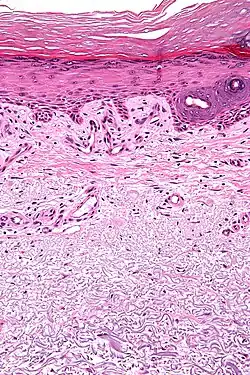

| Micrograph showing solar elastosis - grey, jumbled spaghetti-like material on bottom of image. H&E stain. | |

In the earlier stages of actinic elastosis, elastic fiber proliferation can be seen in the dermis. As the condition becomes more established, the collagen fibers of the papillary dermis and reticular dermis become increasingly replaced by thickened and curled fibers that form tangled masses and appear basophilic under routine haematoxylin and eosin staining. These fibers stain black with the Verhoeff stain.[2]